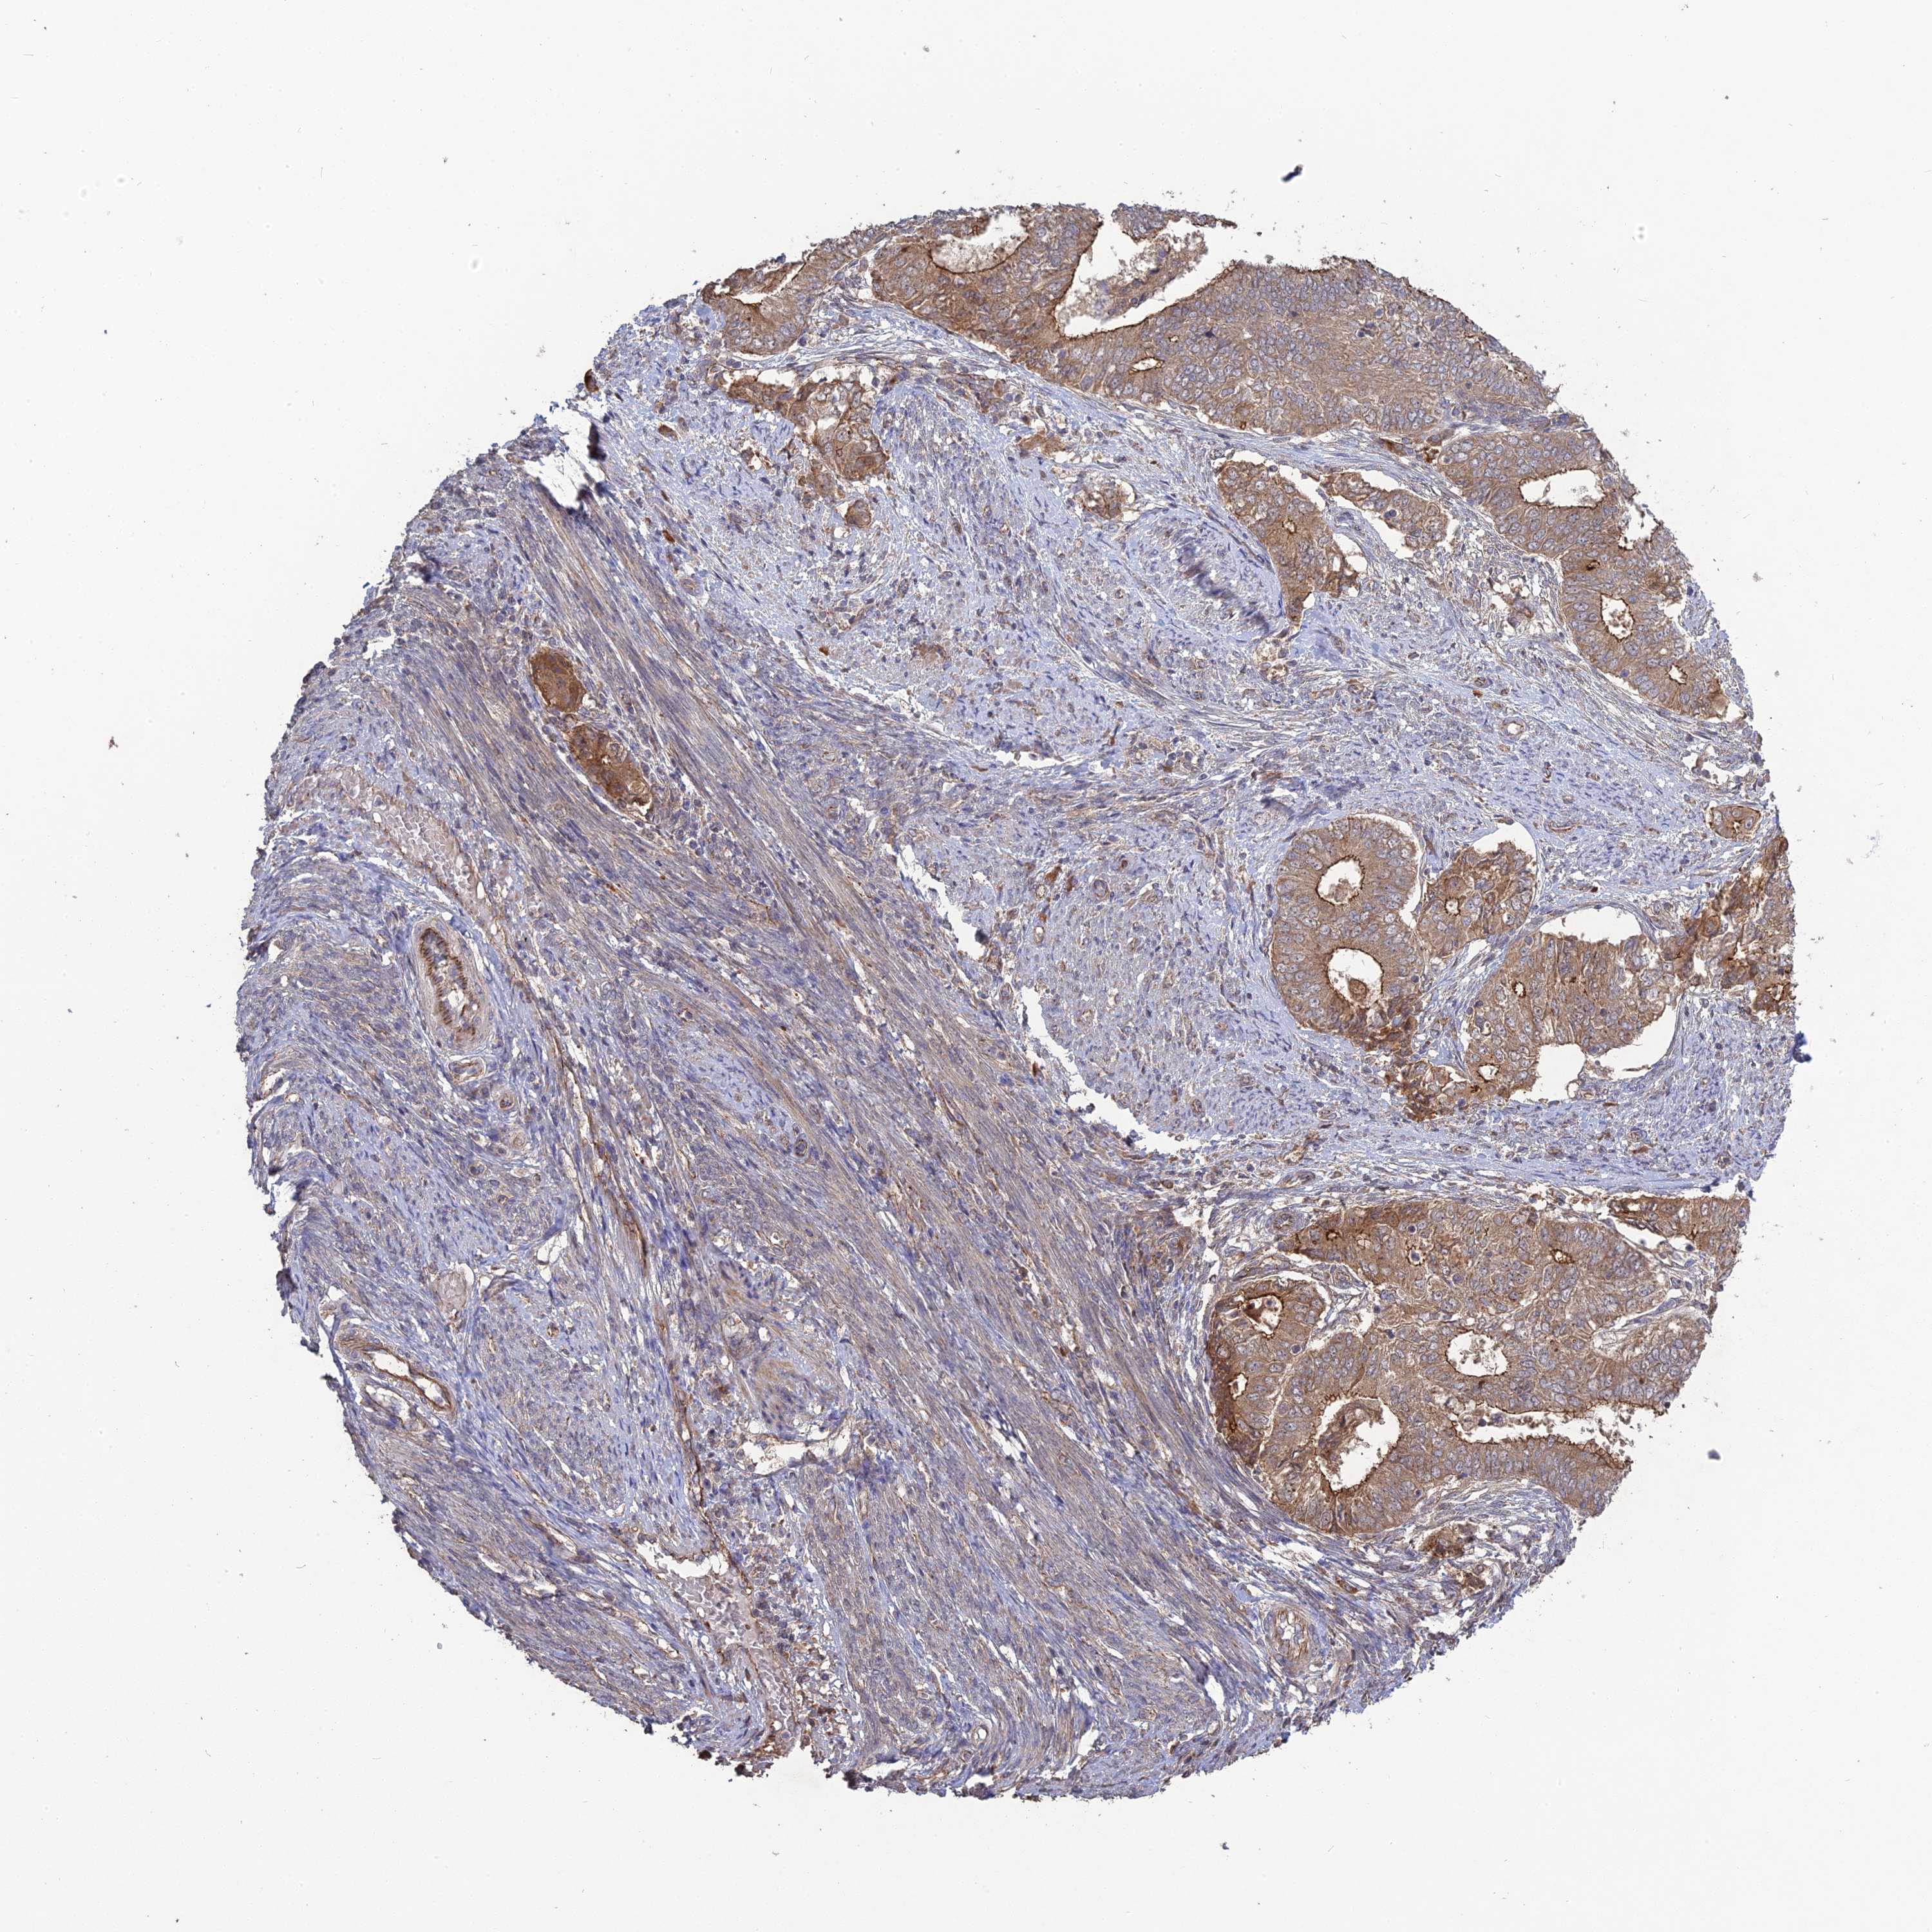

ENDOMETRIAL CANCER - Protein expressioni

A mouse-over function shows sample information and annotation data. Click on an image to view it in a full screen mode. Samples can be filtered based on level of antibody staining by selecting one or several of the following categories: high, medium, low and not detected. The assay and annotation is described here.

Note that samples used for immunohistochemistry by the Human Protein Atlas do not correspond to samples in the TCGA dataset.

Antibody stainingi

Antibody staining in the annotated cell types in the current human tissue is reported as not detected, low, medium, or high, based on conventional immunohistochemistry profiling in selected tissues. This score is based on the combination of the staining intensity and fraction of stained cells.

Each image is clickable and will lead to virtual microscopy that enables deeper exploration of all samples and also displays staining intensity scores, fraction scores and subcellular localization as well as patient and tissue information for each sample.

Antibody HPA042636

Antibody HPA042840

Staining

High

Medium

Low

Not detected

Intensity

Strong

Moderate

Weak

Negative

Quantity

>75%

75%-25%

<25%

None

Location

Nuclear

Cytoplasmic/membranous

Cytoplasmic/membranous,nuclear

Adenocarcinoma, NOS